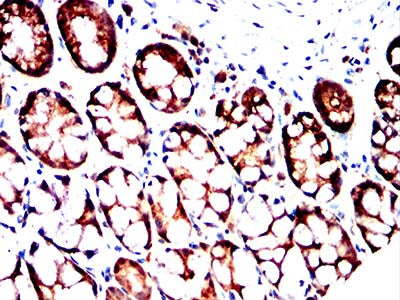

Immunohistochemical analysis of paraffin-embedded human colon cancer tissues using MRP3 mouse mAb with DAB staining.